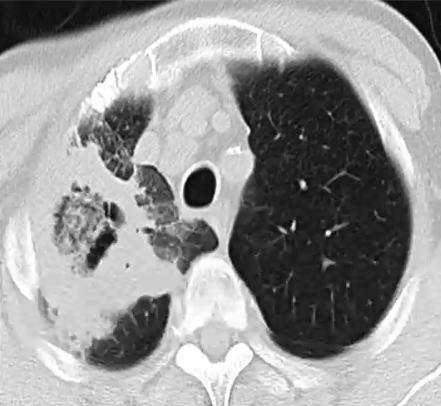

反晕征(reversed halo sign, RHS)

❖ 定义:局限性、圆形磨玻璃影被环状的实变影包绕

❖ 真菌感染中,RHS常见于毛霉菌感染

❖ 也有报道:RHS最常见于快速进展的曲霉菌,其次为毛霉菌感染